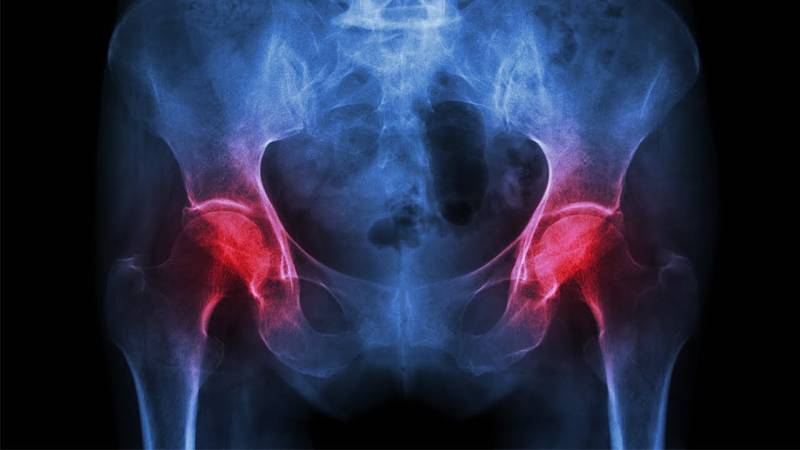

4-هشاشة العظام

أوردت المجلة أن هشاشة العظام تعتبر مرضا عظميا، حيث غالبًا ما يكون الشخص المصاب غير مدرك لحالته. نظرًا لعدم ظهور أي علامات أو أعراض على الإطلاق، حتى يخضعوا بالطبع لكسر ويتم التشخيص. وهذا هو سبب تسميته أيضًا بالقاتل الصامت، إلى جانب التأثير على كثافة العظام، يمكن أن يؤثر أيضًا على صحة الفم.

إن تناول الأطعمة الغنية بالكالسيوم وفيتامين د، أمر ضروري للوقاية من أي شكل من أشكال أمراض العظام، يجب على المرء أن يخوض تمارين. بما في ذلك المشي والركض وصعود السلالم وتدريب الأثقال وما إلى ذلك. كما يُنصح أيضًا بإجراء فحوصات منتظمة.